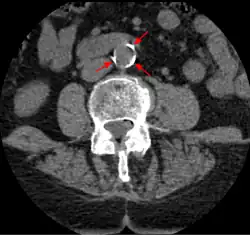

W 2013 ogłoszono wyniki badań 137 ciał zmumifikowanych wskutek działań ludzi bądź w sposób naturalny. Pochodziły one z czterech antycznych społeczności: Egipcjan, mieszkańców dzisiejszego Peru, Indian Anasazi oraz Aleutów. Wyniki badań tomograficznych dostarczyły danych o częstości występowania tej choroby w warunkach dużo mniej zaawansowanej cywilizacji i u ludzi prowadzących bardzo różne tryby życia (od rolniczych do zbieracko-łowieckich). U 34% mumii zdiagnozowano miażdżycę pewną (zidentyfikowane zwapnienia tętnic) bądź miażdżycę prawdopodobną (zidentyfikowane zwapnienia w spodziewanej lokalizacji tętnic). Najrzadziej (25% z 51 mumii) występowała u Peruwiańczyków, najczęściej u Aleutów (60% spośród 5 mumii). Stwierdzono również statystycznie istotną, pozytywną korelację szacowanego wieku w chwili śmierci i występowania choroby: zmarli z miażdżycą byli średnio starsi w momencie śmierci od zmarłych bez miażdżycy[14][15]. Komentujący uczeni wskazywali, że odkrycie jest istotne w kontekście często wyrażanego poglądu, że miażdżyca jest konsekwencją współczesnego, niezdrowego trybu życia. Wskazuje ono na znaczenie innych czynników, które dawniej powodowały tę chorobę. Jednym z nich mogły być stany zapalne, na przykład wywołane ciągłym wdychaniem dymu albo chronicznymi infekcjami[14].